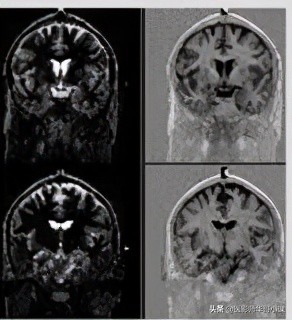

模图采集,只关心矢量的大小,不关心其方向(即是正矢量还是负矢量),那么对应到灰阶时就是,量的绝对值越大,越白;绝对值越小(即越接近于零矢量),越黑。我们对照模图M来看,在脑白质过零时采集,那么由于脂肪比脑白质弛豫快,那么其矢量已经恢复到正方向且有较大的值 ,在M图上表现为较高信号(亮);脑灰质由于比脑白质弛豫慢,那么采集时其仍在恢复,但其还没有达到零,仍有较少的负矢量,那么在M图上表现为稍高信号(灰);脑脊液由于拥有很长的T1值,那么其弛豫是非常慢的,采集时,其仍拥有很大的负矢量,那么在M图上就表现为高信号(亮);但由于采集时脑白质刚过零,那么其矢量为零,在M图像上就对应最黑,跟空气差不多(背景是黑色),即无信号。

实图采集,不仅关心矢量的大小,也关心其方向(即是正矢量还是负矢量),那么对应到灰阶时就是,最大正矢量对应最白;最大负矢量对应最黑,零矢量对应正中间的灰色,即背景为灰色(空气是没有信号的)。我们对照实图R来看,在脑白质过零时采集,那么由于脂肪比脑白质弛豫快,那么其矢量已经恢复到正方向且有较大的值,在R图上表现为较高信号对应到灰到白的灰阶,即亮白;脑灰质由于比脑白质弛豫慢,那么采集时其仍在恢复,但其还没有达到零,仍有较少的负矢量,那么在M图上表现为较低信号,对应着灰到黑的灰阶,即灰黑色;脑脊液由于拥有很长的T1值,那么其弛豫是非常慢的,采集时,其仍拥有很大的负矢量,那么在R图上就表现为更低的信号,趋于黑色;但由于采集时脑白质刚过零,那么其矢量为零,在R图像上就对应灰色,跟背景一个灰阶。

好了,实图与模图已经搞清楚了。那么我提个问题,我们常规的颅脑T1反转恢复序列一般都是采用的模图M,那么其TI反转时间是多少呢?能根据信号公式计算出最优时间吗?还有就是研究过了这个序列,就会立马想到STIR,FLAIR序列跟这个不是一个大家庭的吗?可谓不攻自破(“不研即会”)。接着,就会想到进阶序列,双反转、三反转等。